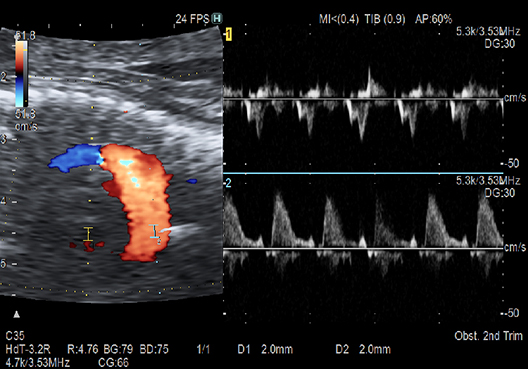

Enables observation of Doppler waveforms from two different locations during the same plane. The rhythm of atrial and ventricle contraction can be evaluated more easily than conventional methods.